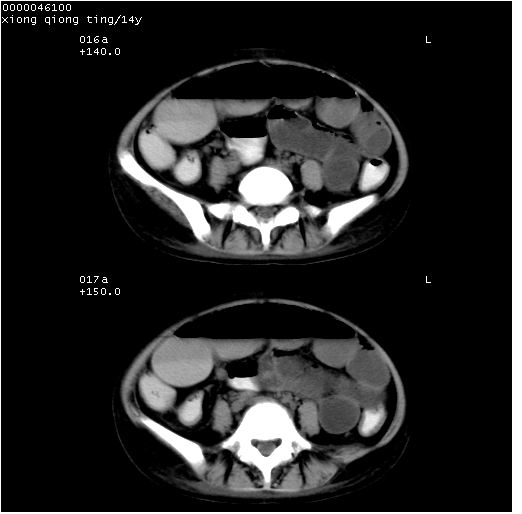

中下腹及盆腔ct轴位平扫+增强扫描(层厚10mm,螺距1.0,重建间隔10mm),图像如下:

(注:患儿检查当日上午9时口服胃肠道对比剂,下午3时许行ct扫描检查,未行对比剂直肠保留灌肠,检查当日患儿腹泻)

中下腹及盆腔ct轴位扫描(ps+ce)提示:腹部肠管明显充气扩张,并见数个不同宽度之气液平面;疑不全性肠梗阻或肠郁张。临床会诊考虑为患儿腹泻,肠郁张所致;后来未经特殊处理,患儿大便恢复正常,亦无腹胀。